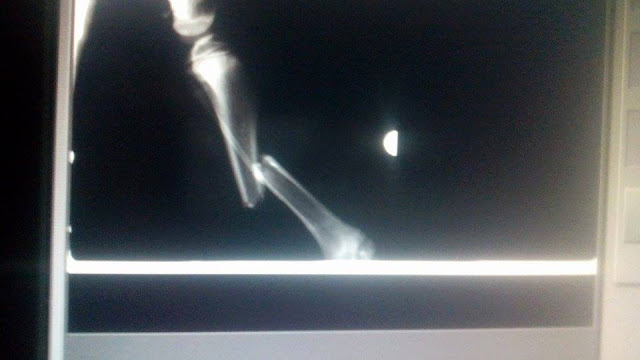

1 καταγμα η Κλειω και 3 ο Buter στα ποδια

Ο Buter χτυπηθηκε στο κεφαλι και η Κλειω εχει σχισμενο βλεφαρο

Η Κλειω έχει συντριπτικό κάταγμα μηριαιου με παρεκτοπηση.

Θα πρεπει να γίνει χειρουργική αναταξη με πλάκα.

Ο Butter έχει συντριπτικό κάταγμα μηριαιου με παρεκτοπηση και αμφοτεροπλευρο κάταγμα κνημης περονης. Ιδια διαδικασία αναταξης.

Ειναι στην ουσια 4 χειρουργεια και το κόστος είναι 800 ευρώ.